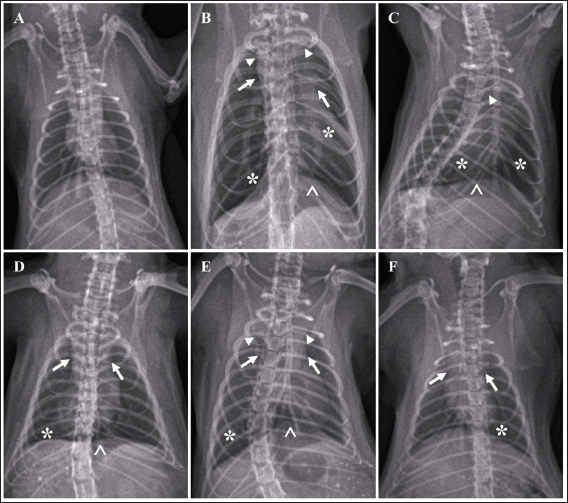

Score of lung imaging

A significant difference was found between group G2 (untreated) and group G1 in terms of lung radiograph scores (p < 0.05). Groups G3 and G5 exhibited lung radiographs similar to those of group G2 (p > 0.05). Moreover, groups G4 and G6 showed lung repair after treatment compared to group G2 (p < 0.05). In several parameters, groups G4 and G6 did not exhibit differences compared to G1, especially in lung retraction scores and pleural effusion (p > 0.05). Group G6 also displayed better outcomes in lung radiographs than G4, particularly regarding the alveolar pattern and widened mediastinum (p < 0.05). Furthermore, group G6 did not differ from G1 in terms of mediastinal lesions (p > 0.05) (Table 4). A qualitative assessment of the lung radiograph is presented in Figure 3.

Fig. 3. Radiograph of rats’ lung after treatment. Typical lung image of the healthy rats from group G1 (A); the infected rat without treatment from group G2 showed a diffuse lesion on the lung marked by the widened of the mediastinum (arrow) with the retraction of the caudal portion of the lung (arrowhead), alveolar pattern (*) with the pleural effusion (^) (B); the group G3 showed the similar radiographic pattern with group G2 (C); group G4 indicated the focal alveolar pattern (*) with minimal pleural effusion (^) and mediastinum is widened (arrow) (D); moderate lesion of the lung from group G5 marked by widened of mediastinum (arrow), lung retraction (arrowhead), lobular alveolar lesion (*) with pleural effusion (^) (E); and minimal alveolar lesion (*) and the retraction of lung and widened of mediastinum still observed (arrow) from group G6 (F).